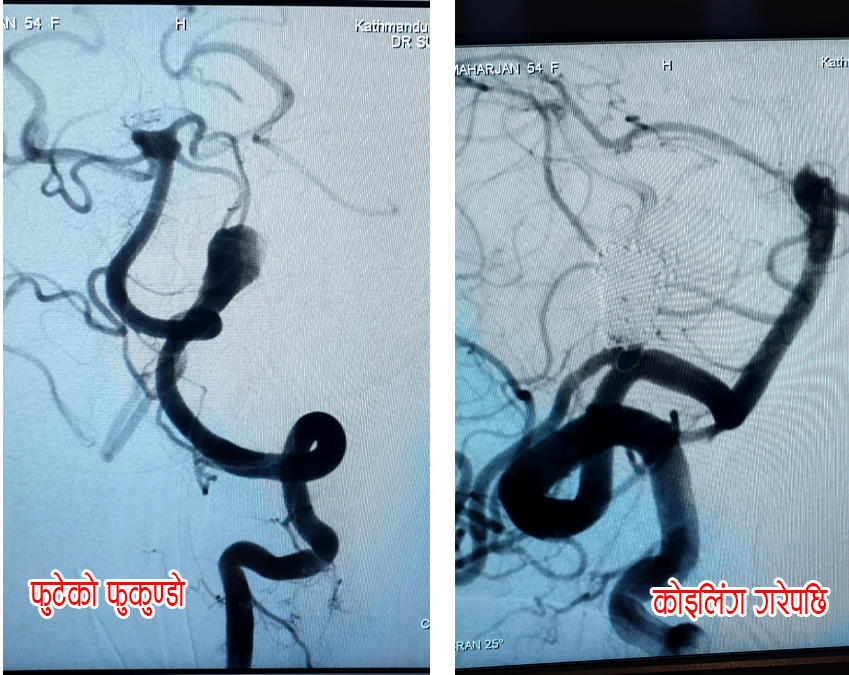

काठमाडौं, १४ कार्तिक । काठमाडौं मेडिकल कलेजमा ६० वर्षीया महिलाको न्युरो इन्डोभास्कुलर कोइलिङद्वारा मस्तिष्कको शल्यक्रिया नगरी सफलतापूर्वक उपचार गरिएको छ । केएमसीका इन्टरवेंशनल न्यूरोलोजिस्ट डाक्टर समर्थ सिंहको नेतृत्वमा काठमाडौंकी ६० वर्षीय महिलाको टाउकाको चिरफार नगरीकन न्युरो इन्डोभास्कुलर कोइलिङ प्रविधिबाट उपचार गरिएको हो ।

ब्रेन हेमोरेज-सबएरेकनोइड हेमोरेज भएर आएकी ती महिलाको रक्तनलीबाट मस्तिस्कमा पुगेर ब्लक भएको रक्तनली खुलाइएको इन्टरवेंशनल न्यूरोलोजिस्ट डाक्टर समर्थ सिंहले जानकारी दिए । ‘एक महिना अगाडी उहाँलाई ब्रेन ह्याम्रेज भएर केएमसीमा ल्याइएको थियो । बिरामीको ब्रेनको पछिलो भागको रक्तनलीमा फूकुन्डो, जसलाई ब्रेन अनेउरीसम भनिन्छ, फुटेर मस्तिस्कमा रक्तस्राव भएकाे थियो । हामीले न्युरो इन्डोभास्कुलर कोइलिङ प्रविधिबाट बिरामीको टाउको नचिरीकन सफलतापूर्वक कॉइलिंग पद्धतिबाट सो फुटेको फुकुन्दोमा रक्तप्रवाह बन्द गरेर सफलतापूर्वक उपचार गर्यौं ।’ डा. सिंहले भने ।